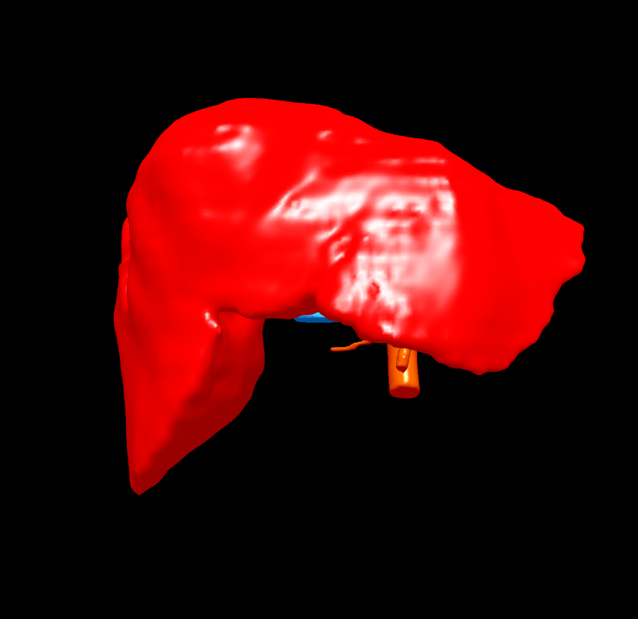

右肝癌复发-门静脉栓塞+肿瘤动脉栓塞后右半肝切除